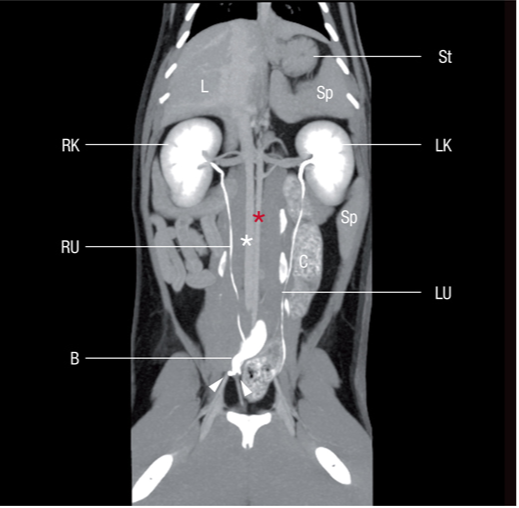

猫的右肾位于肝脏尾叶部位的肾窝位置。右侧肾上腺,后腔静脉,腹壁侧面边界都是右肾的解剖学参照物。因为猫的肾脏有很大的移动性,而且做肾脏超生检查时猫的肝脏有时也不是很明显。左肾位于胃底的尾部和脾脏前部内侧。左侧的肾上腺以及主动脉是左肾的参照物。同时降结肠是左肾腹侧的参照物。侧面的边界就是腹壁(图2)。

肝脏和脾脏的解剖学关系,使得我们可以把肾脏回声和邻近的器官相比较。肾皮质通常对肝脏是等回声或低回声的,对脾脏是低回声的(图3)。

关于输尿管,沿着腹中腰肌走向,盆腔中端平面1-2cm 的侧面,靠近AO 和 CVC(见图.2); 输尿管穿过腹侧面的旋髂深血管和A0 及CVC 的终末分支。在骨盆的水平线上,输尿管沿阔韧带/或生殖器延伸一直到达膀胱三角区。膀胱和输尿管突起在同一水平线上。输尿管突起影像中可以看到是膀胱壁上的一个小团块。输尿管的喷射可以观察到反射波漩涡的图像,这个影像位于膀胱三角区至膀胱内腔的区域(图5.视频2)。健康猫输尿管的管腔直径是0.4 mm并且通过超声波很难观察到。有-点很重要:尿液是通过蠕动和收缩来流动的,因此只有当输尿管扩张的时候才能通过超声波观察。